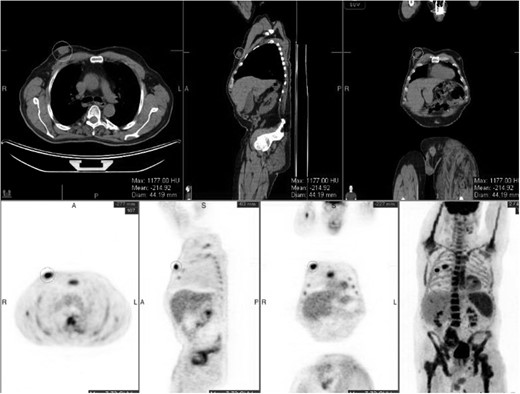

Staging positron emission tomography computed tomography (PET CT) was performed demonstrating activity in the right breast as well as mediastinal and hilar lymphadenopathy (Fig. 2). The patient underwent neoadjuvant chemotherapy and a repeat PET CT showed decreased activity in the right breast and no further lymphadenopathy (Fig. 3). A right modified radical mastectomy was performed. Pathologic examination revealed invasive ductal carcinoma, histologic grade III with closest margin at 1mm away. There was 0 out of 18 positive axillary lymph nodes. Pathologic staging was set at pT2N0M0, Stage IIA. Given the slim posterior margin, he received post mastectomy radiation therapy. Currently, the patient is receiving tamoxifen 20 mg once a day.

Preoperative staging CT scan. Chest wall mass noted to be 6.9 cm × 2 cm.